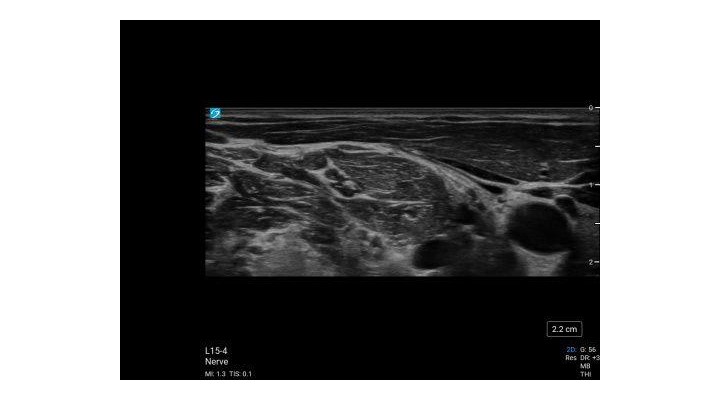

- Begin by placing the ultrasound transducer subcostal at the anterior axillary line.

- The external oblique, internal oblique and transversus abdominis muscles should be identified.

L12-3, L15-4